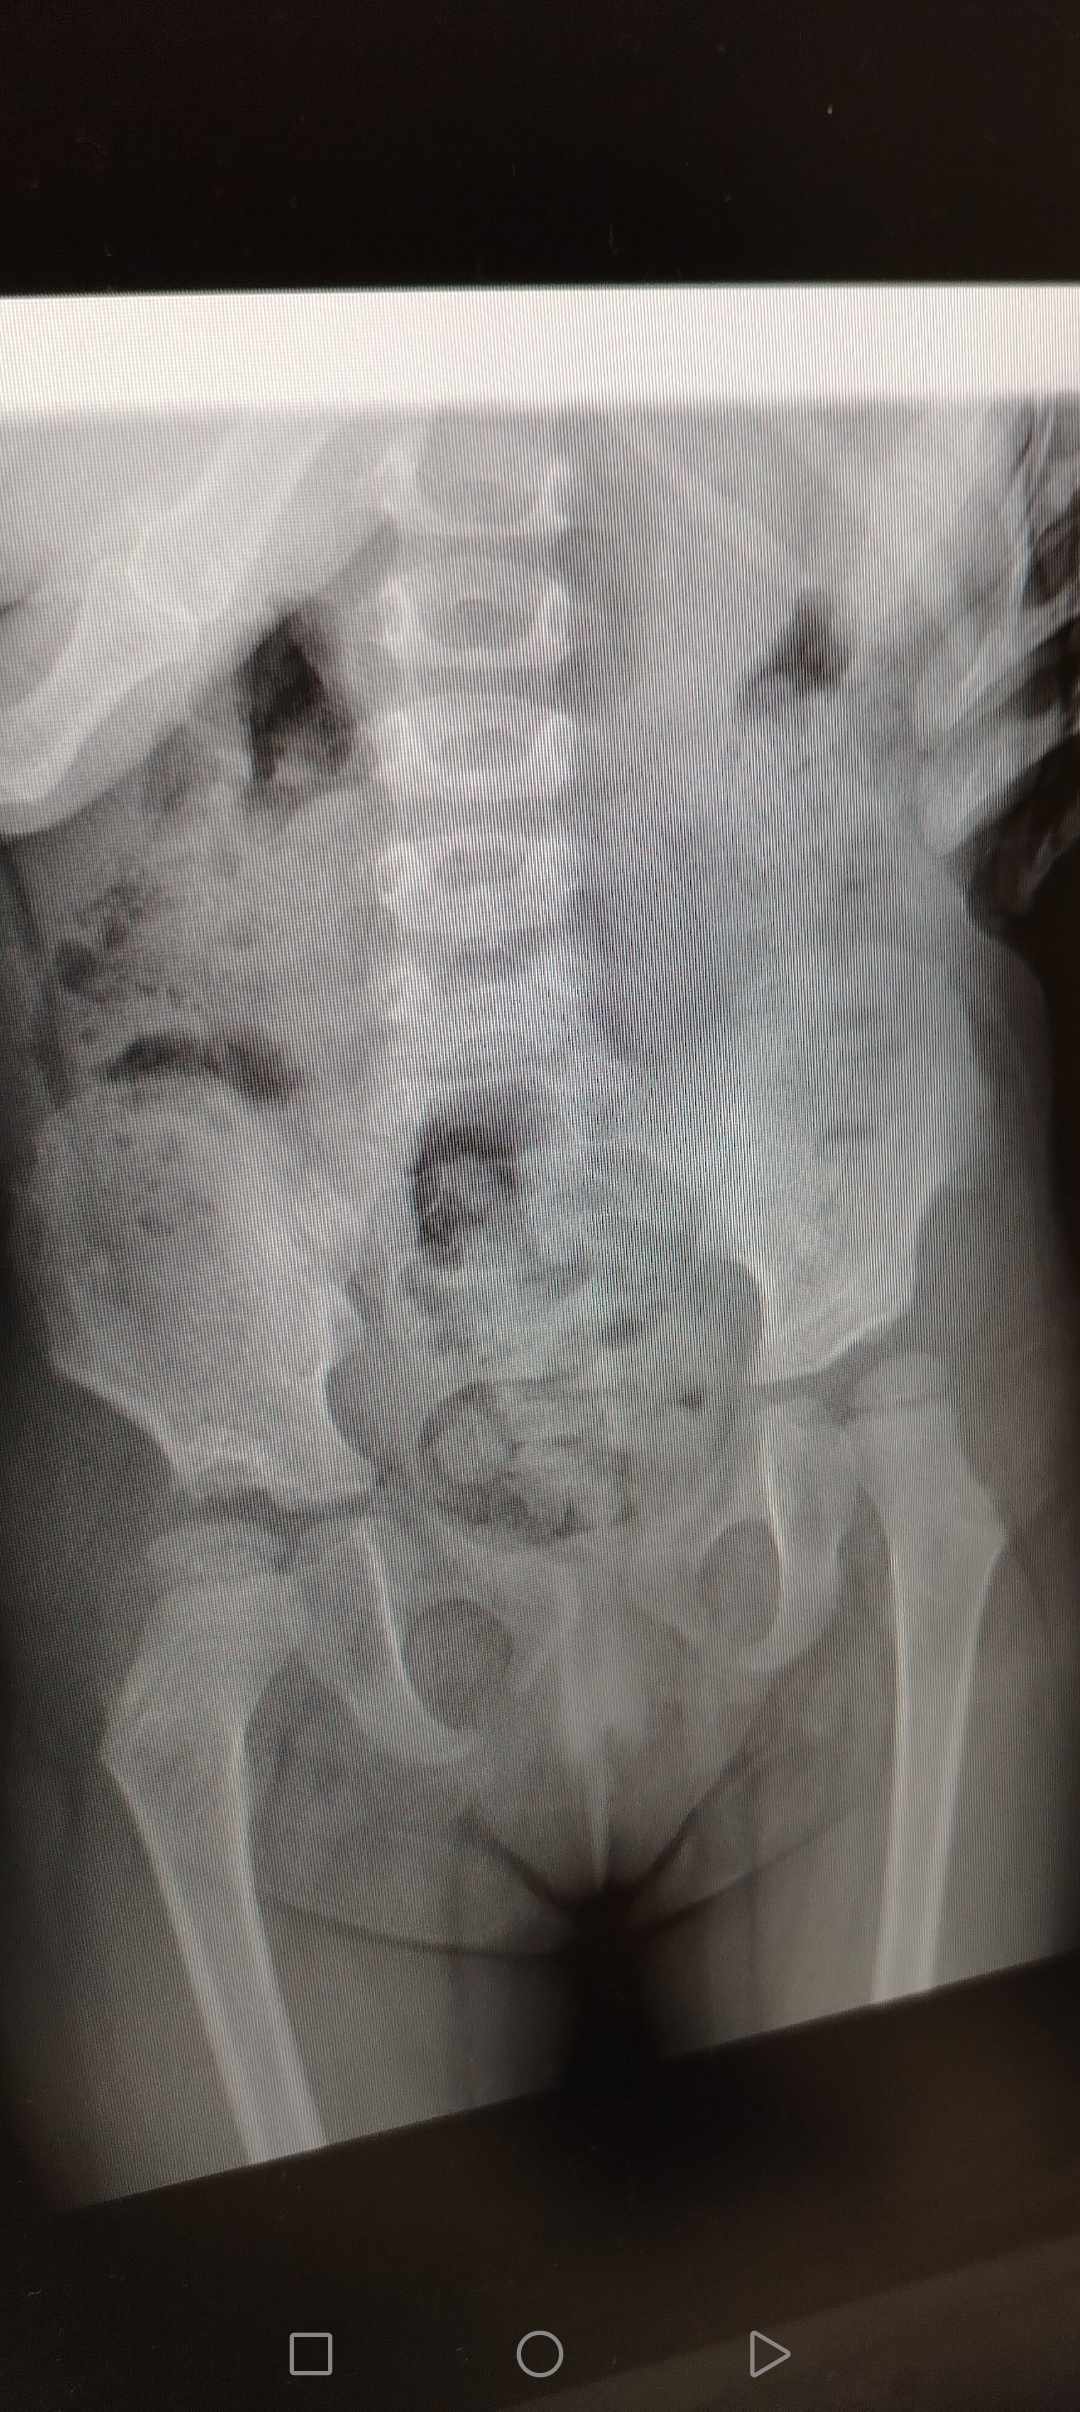

صورة خلع الولادة بعد العملية الجراحية

ارجو منكم تقيم الصوره لخلع الولاده بعد إجراء عمليتين

صورة خلع الولادة بعد العملية

شاهدت الصورة

والوضع جيد

ولا توجد علامات خلع

ولكن هناك آثار العمل الجراحي وهذا طبيعي

واحتواء رأس الفخذ ضمن جوف الحُق ممتاز

وزوايا المفصل طبيعية

وعودة الخلع مستبعدة جداً

والمطلوب متابعة عادية فقط